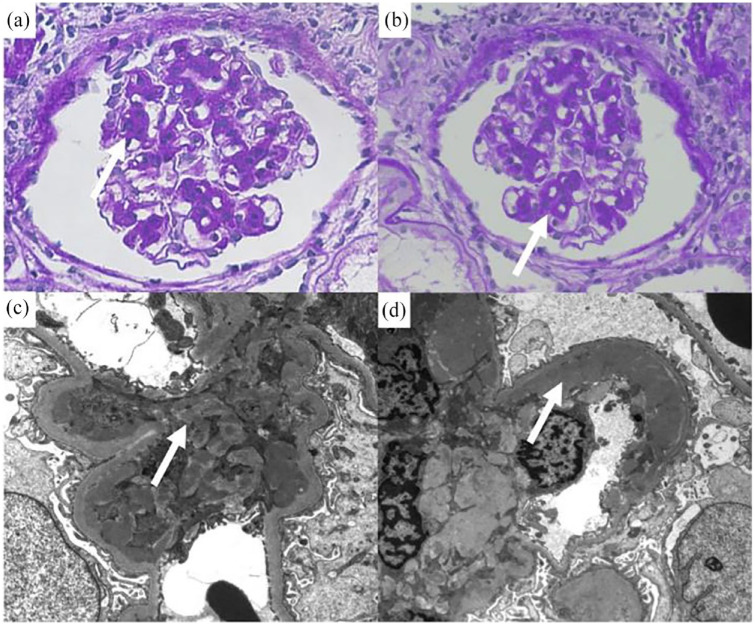

本研究报告了一例56岁日本男性在治疗免疫性血小板减少性紫癜(ITP)期间观察到的免疫复合物介导的系膜增生性肾小球肾炎(ICGN)的罕见病例。由于持续的补体缺乏和肾功能的恶化,他接受了强的松龙治疗,他的泌尿系统检查结果明显改善。然而,由于补体滴度仍然很低,也开了霉酚酸酯,使补体水平正常化。抗血小板抗体的产生被认为与ITP的病因有关。尽管对ITP引起肾小球肾炎(包括ICGN)的机制知之甚少,但抗血小板抗体合成的循环免疫复合物的肾小球沉积可能参与其中。该病例表现为全屋肾病,提示免疫复合物的参与,这反过来提示ITP与肾小球肾炎之间的关联。

This study reports a rare case of immune-complex mediated mesangial proliferative glomerulonephritis (ICGN) with a full-house pattern in a 56-year-old Japanese man, observed during the treatment of immune thrombocytopenic purpura (ITP). Because of persistent complement deficiency and worsening of kidney function, he was treated with prednisolone, and his urinary findings improved markedly. However, as the complement titers were still low, mycophenolate mofetil was also prescribed, which normalized complement levels. Production of anti-platelet antibodies is considered to be involved in the etiology of ITP. Although little is known about the mechanism by which ITP causes glomerulonephritis, including ICGN, glomerular deposition of circulating immune complexes synthesized by antiplatelet antibodies may be involved. This case shows full-house nephropathy, suggesting the involvement of immune complexes, which in turn, suggested an association between ITP and glomerulonephritis.